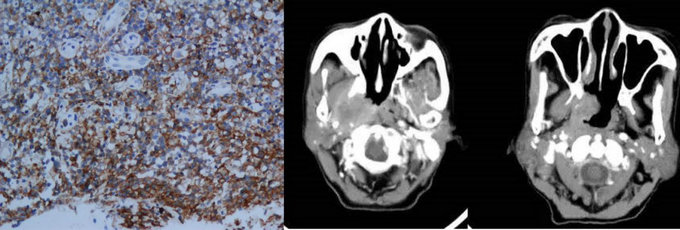

NK/T淋巴瘤病理及影像表现